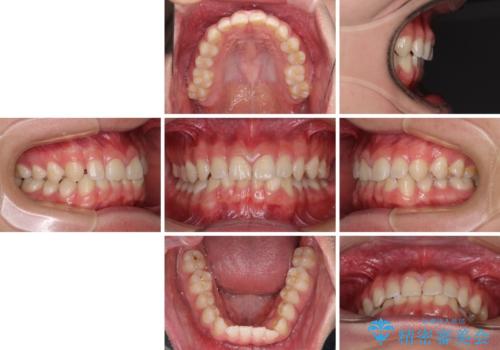

隙間とデコボコを治したい ワイヤー装置による矯正治療

- 前歯のデコボコと隙間を気にして来院された患者様です。

治療手段としてはワイヤー装置でもインビザラインでも可能でしたが、インビザラインの自己管理は自信がないとのことで、ワイヤー矯正により隙間を閉じていくこととしました。

隙間の原因は舌の突出癖であったので、舌癖改善のためのトレーニングを指導しながら治療を進めて行くこととしました。

舌の突出癖がなかなか改善されず、治療開始時よりも隙間が大きく開いてしまう時期がありましたが、最終的にしっかりと閉じて終了することができました。